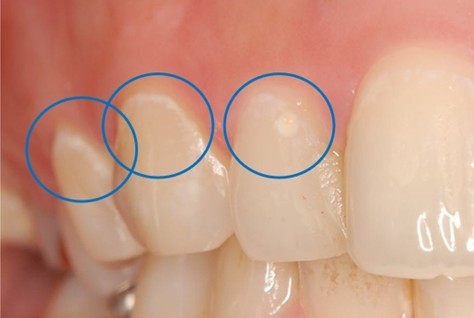

さらに注意したいのが、"ホワイトスポット(歯の白い濁り)"です。

【ホワイトスポットとは?】

歯の表面にみがき残しがあると、歯の表面のミネラルが溶けてしまい、歯が白く濁ったように見える状態(初期むし歯)になることがあります。